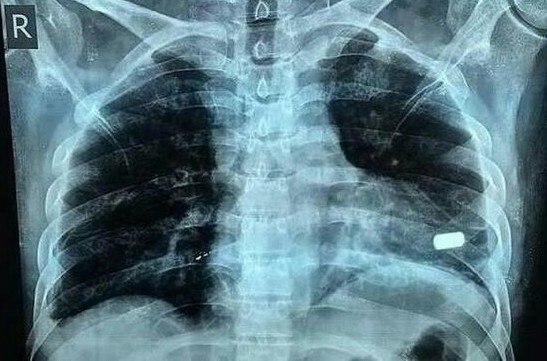

Фото - ілюстративне

— За дрібне зауваження і такого наробив! Хай тепер відповідає по повній. Він три кулі в мене всадив! Ту, що пробила легені, прилуцькі хірурги витяти, а ще дві увійшли глибоко, тож їх поки що не діставали. Одна застрягла в стопі біля кістки, а друга — в ребрі. Я сама відпросилася з лікарні додому. Хоча ходити мені ще боляче, але нічого, справляюся. Малий онде перев’язки мені робить... Скандали в нас із чоловіком і раніше були, каструлі літали. Але ж до такого не доходило.